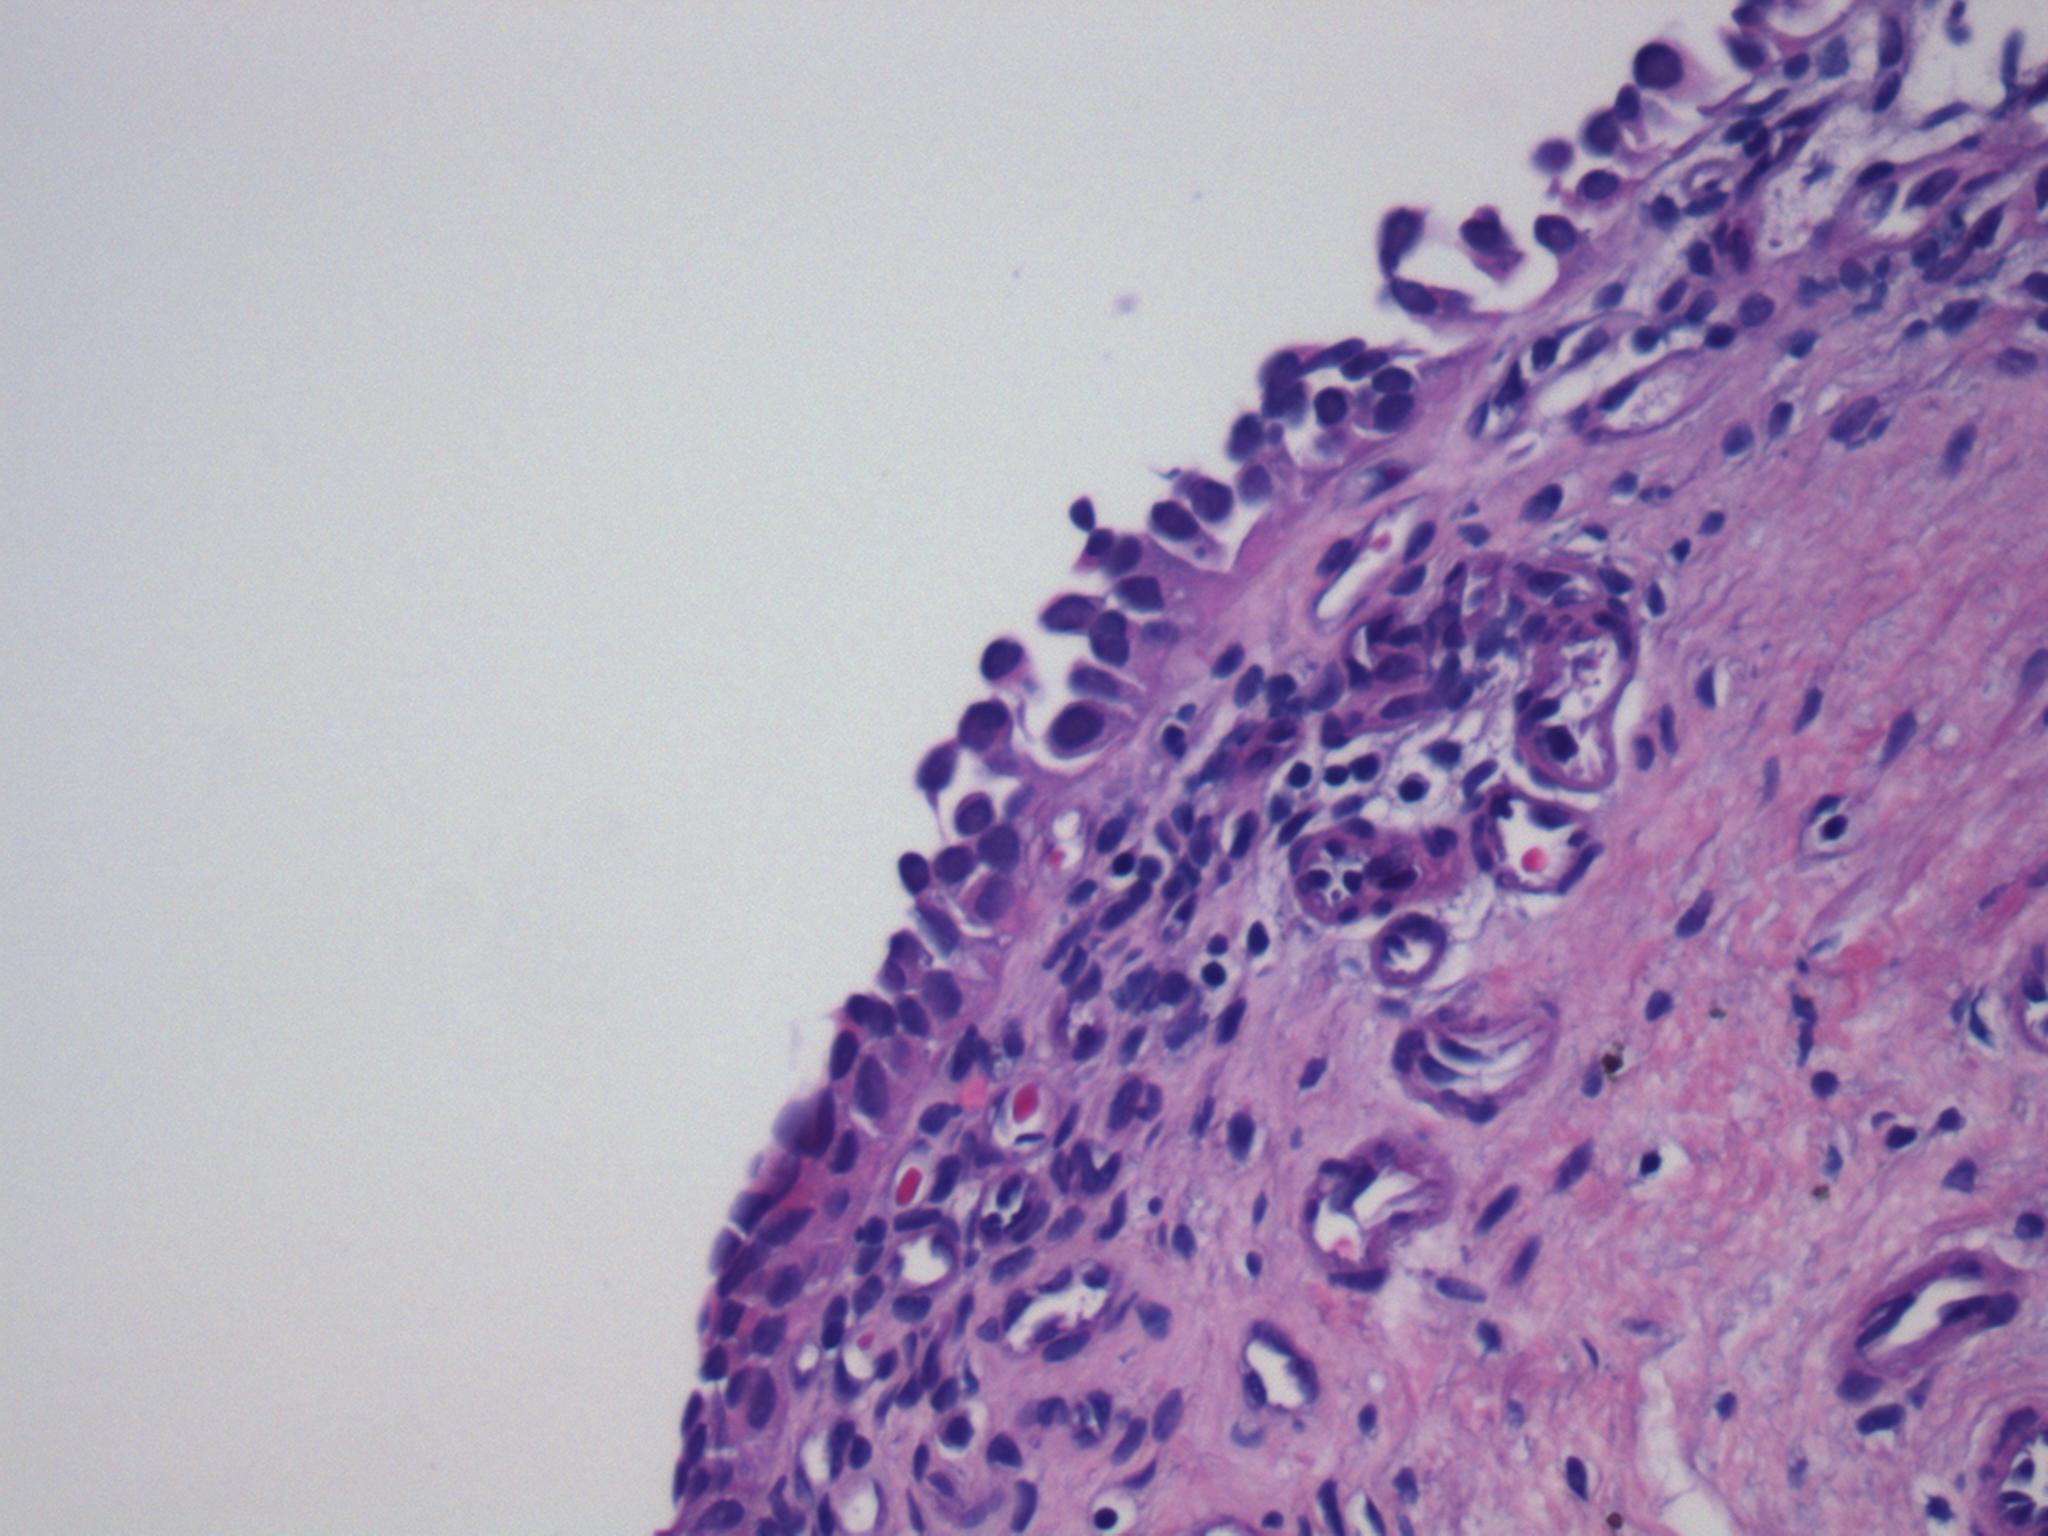

Consensus grade: Carcinoma in situ (CIS)

Prominent loss of cohesion of highly atypical urothelial cells